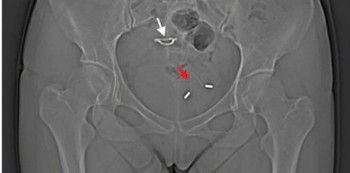

Setelah mendapat laporan ada masalah dengan kandung kemihnya, dokter di rumah sakit Jilin University melakukan pemeriksaan rontgen pada panggul ibu yang tidak disebutkan namanya tersebut. Hal mengejutkan pun terjadi, KB IUD yang dulu dinyatakan hilang terlihat dalam hasil rontgen.

Dari hasil pemeriksaan sinar X, terlihat bahwa ada dua KB IUD yang tertanam di dalam tubuh pasien tersebut. Satu yang baru saja dimasukkan setelah operasi cesar, dan satu lagi KB IUD berpindah tempat ke dalam kandung kemihnya.